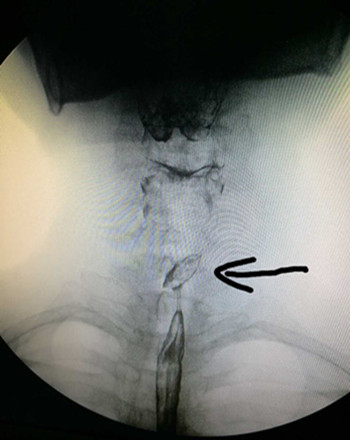

患者来我院就诊时,咽痛严重,饮水时有哽噎感,4天来未进饮食,身体非常虚弱。遂抱着试一试的心态来到我院耳鼻咽喉科门诊就诊,张立刚副主任看过患者后经过综合评定,认为我院已具备此例手术条件,门诊遂以“食管异物”收住入院。入院后张立刚副主任立即组织安排手术前相关检查事项,急查上消化道造影提示:食道(约第3胸椎水平)可见一椭圆形异物。尚规划主治医生立即给予积极完善相关检查、补液、消肿,待患者基础情况好转,能耐受手术后,急诊在全身麻醉下行食管内异物取除术,用硬质食管镜直视下发现枣核两端还是横向扎在食道壁,此处离主动脉弓只有不到2cm,稍有不慎即可损伤主动脉造成无法控制的大出血,或者引起食道穿孔,与术前评估情况没有差异。张立刚副主任沉着冷静,尚规划医生一丝不苟,在两人默契配合下,顺利将枣核取出。术后患者在耳鼻咽喉科医护团队的细心治疗与护理下于迅速康复出院。此例经硬质食道镜成功取异物病例填补了我院硬质食道镜取除食道异物的空白。